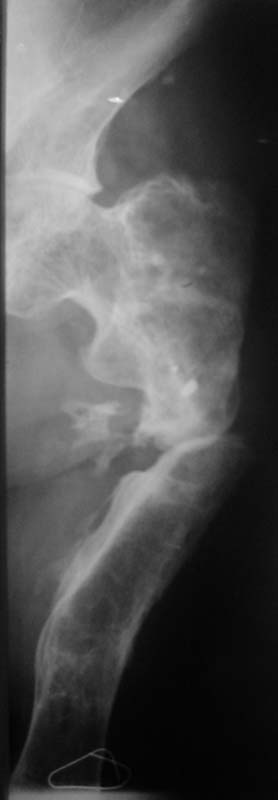

Просится "русский замок" с последующим удлинением на двух уровнях. Нельзя ли посмотреть тазобедренный сустав?